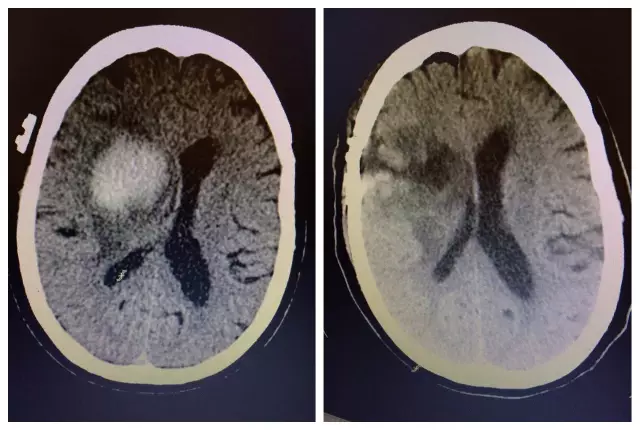

46歲的劉先生平時(shí)算健康,但是血壓卻控制不好,未規(guī)律服藥。一天在吃著飯時(shí),他突然倒地,意識(shí)不清、左半身手腳僵直、無法說話。家人連忙撥打了120,將他送往惠州市第三人民醫(yī)院治療。入院時(shí),劉先生的血壓值竟達(dá)到210/128mmHg,做了顱腦CT檢查后被確診為腦出血。神經(jīng)外科醫(yī)生對(duì)其進(jìn)行了急救手術(shù),最終保住了性命,但不幸得是,遺留下了后遺癥——偏癱。![]()

術(shù)前后CT惠州三院神經(jīng)醫(yī)學(xué)中心神經(jīng)外科負(fù)責(zé)人景英朝主任醫(yī)師介紹,這樣的高血壓腦出血患者不在少數(shù),據(jù)統(tǒng)計(jì)中國(guó)腦出血病人中,約67%合并高血壓,而且未經(jīng)治療的高血壓病人,發(fā)生腦出血的風(fēng)險(xiǎn)是正常人的10倍。即使規(guī)律治療,高血壓病人的出血風(fēng)險(xiǎn)仍然是普通人的2倍!